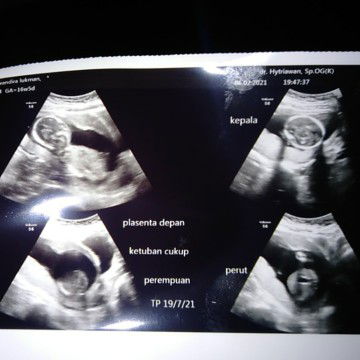

Ibu hamil